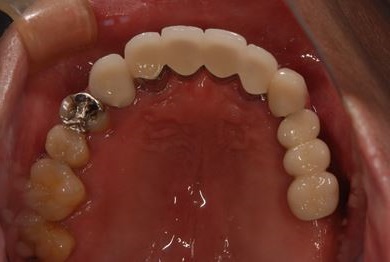

インプラントの症例写真 IMPLANT

骨再生スピードインプラント治療+セラミック治療

| 治療内容 | インプラント4本(ソケットリフト・抜歯即日)、テンポラリーインプラント2本、メタルボンドクラウン9本 | ||||||||||||||||||||||||||||||||

| 総治療費 | 2,025,975円 | ||||||||||||||||||||||||||||||||

| 治療期間 | 1年9ヶ月 |